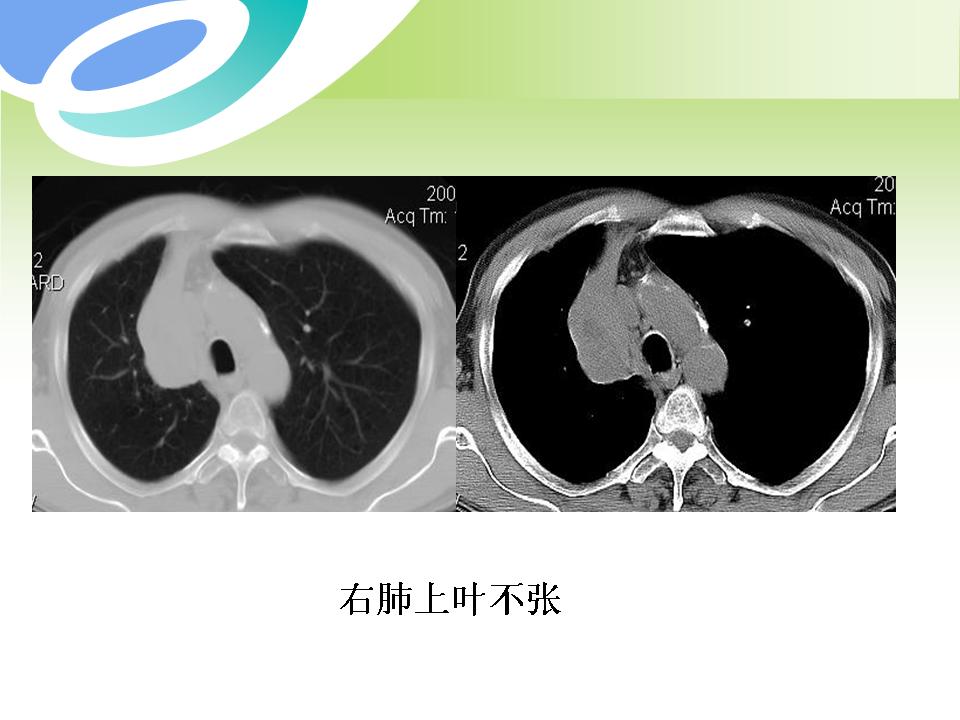

肺部病变的CT基本征象